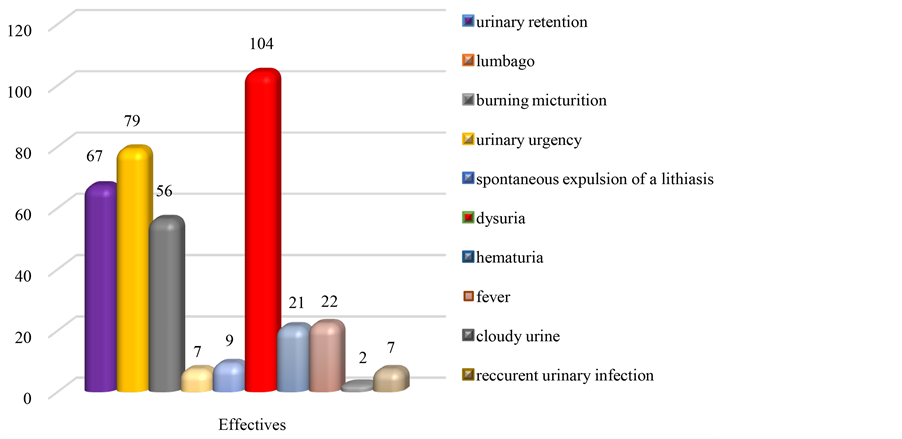

Figure 5. Distribution of patients depending on the reasons for consultation.

The average age of patients was 36 years, ranging from 15 months to 88 years. With a staff of 67 cases or 28.77% of urolithiasis, the age group 0 - 10 years is the most represented, followed by 11 - 20 years and 51 - 60 years (Table 1). Youth 0 - 20 years are most frequently holders of secondary urethral calculi to complications of circumcision. Table 2, Figures 1-3 show the relationship between age and location of the stones. For each age group, the male patients were significant with a sex ratio of 4.5. The distribution by age and sex also shows a male predominance (Figure 4). The socioeconomic level seems to be a predisposing factor to the development of urolithiasis (n = 122 or 52.36%). The stones affected: school students and university students (n = 64 or 27.47%), non-professionals (n = 40 or 17.17%) and middle public officials (n = 36 or 15.45%). The water from traditional wells was used by 91 patients, 110 patients consumed less than one liter of water. Figure 5 reports the different reasons for consultation. Urolithiasis (n = 17) and urogenital bilharzia (n = 11) were found as medical history. The patients diet was rich in meat (n = 200), milk (n = 160), fish (n = 150) and eggs (n = 130).

Clinical symptoms vary between studies and countries as highlighted in Table 4 [1] [6] [7] [10] -[13] .